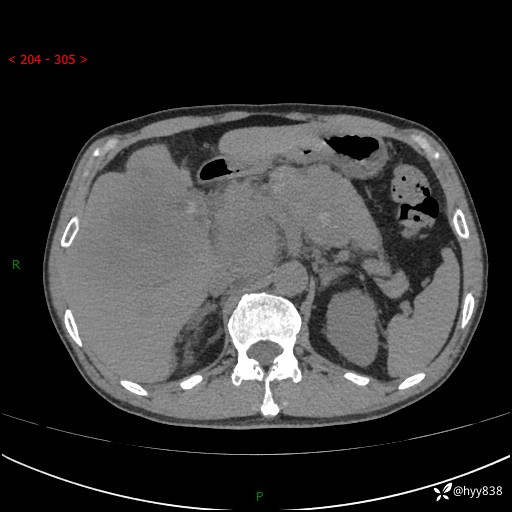

56岁/男,持续性干咳1周余,外院超声发现肝占位,少见病例---结果公布~

现病史:患者1周前无明显诱因出现刺激性干咳,伴食欲减退,无痰,无发热、头晕头痛、恶心呕吐、腹痛腹泻、胸闷喘气、厌油、巩膜黄染等不适,于当地诊所就诊并予以输液治疗,具体不详,患者诉干咳症状稍微好转,现患者为行进一步检查于当地第五人民医院就诊,肝脏彩超提示“肝占位性病变”,遂转入我院门诊就诊,经检查后门诊以“肝占位性病变”收入我科。 患者自起病以来精神、食欲如上述、睡眠一般,大小便正常,近半月内体重降低20余斤,体力无明显下降。

上腹部CT平扫+增强(两期)